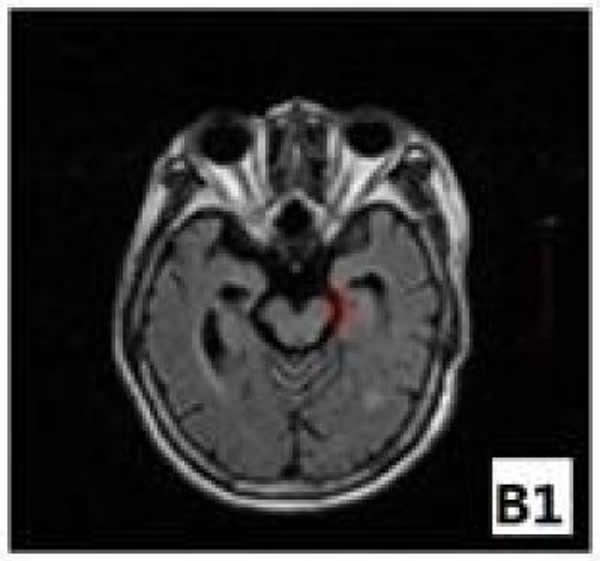

磁共振检测显示,运动诱发电位阴性脑梗死患者患侧大脑脚面积于病后6个月时已经出现大脑脚面积缩小

中国南方医科大学附属小榄医院宋志彬博士所在课题组进行的一项关于“Why do stroke patients with negative motor evoked potential show poor limb motor function recovery?”的研究,重点显示了磁共振诱发电位阴性时脑梗死患者患侧大脑脚各项异性分数值及面积的变化与其肢体功能恢复的关系。结果显示,磁共振运动诱发电位阴性的脑梗死患者患侧大脑脚各向异性分数值低于临界点0.36的时间为发病后1-3个月,患侧大脑脚面积偏侧性下降低于下限值0.83的时间为病后6个月,患侧大脑脚各向异性分数值<0.36及大脑脚面积偏侧性<0.83提示偏瘫肢体运动功能恢复不良。